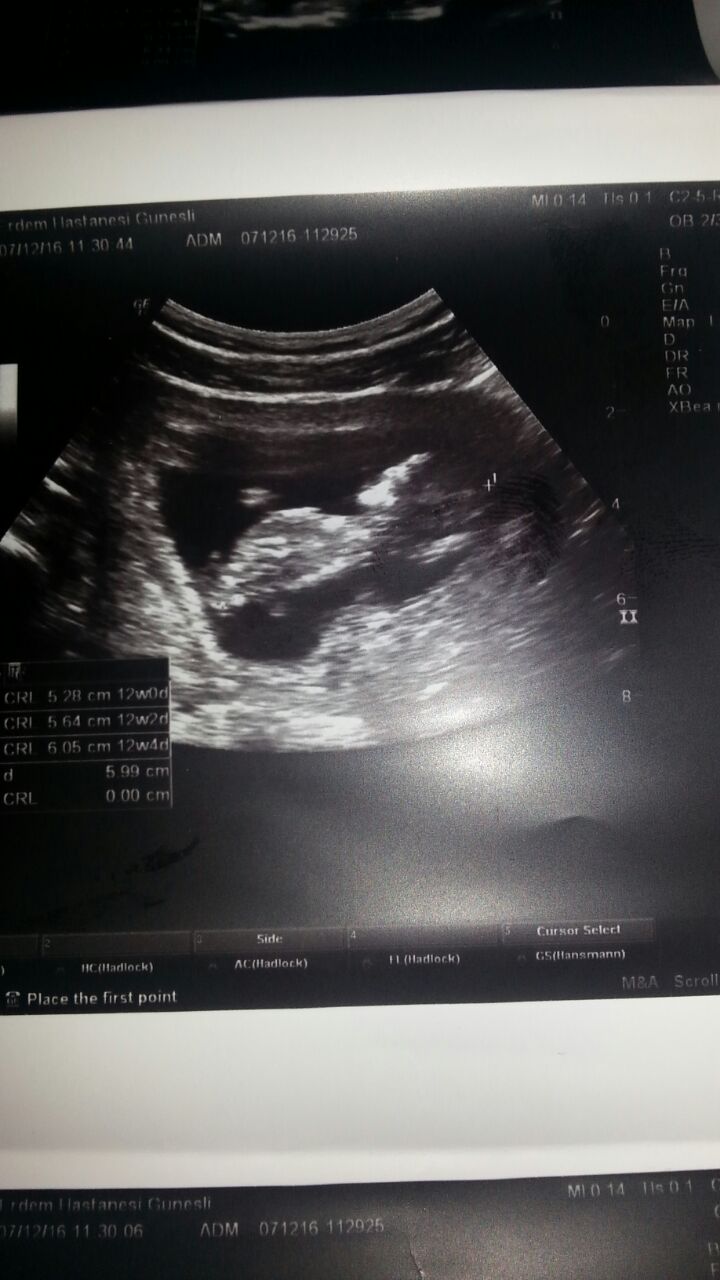

S Sedatunc Yeni Üye Üye 7 Ocak 2017 #118 Lutfenn benimkine de bakar misiniz. Simdiden tesekkur ederim Moderatör tarafında düzenlendi: 8 Ocak 2017

Sevimli cadı Daimi Üye Üye 8 Ocak 2017 #119 Sedatunc' Alıntı: Lutfenn benimkine de bakar misiniz. Simdiden tesekkur ederim Ekli dosyayı görüntüle 73279 Ekli dosyayı görüntüle 73280 Genişletmek için tıkla ... Sizin resimler net değil yorumlayamam malesef

Sedatunc' Alıntı: Lutfenn benimkine de bakar misiniz. Simdiden tesekkur ederim Ekli dosyayı görüntüle 73279 Ekli dosyayı görüntüle 73280 Genişletmek için tıkla ... Sizin resimler net değil yorumlayamam malesef